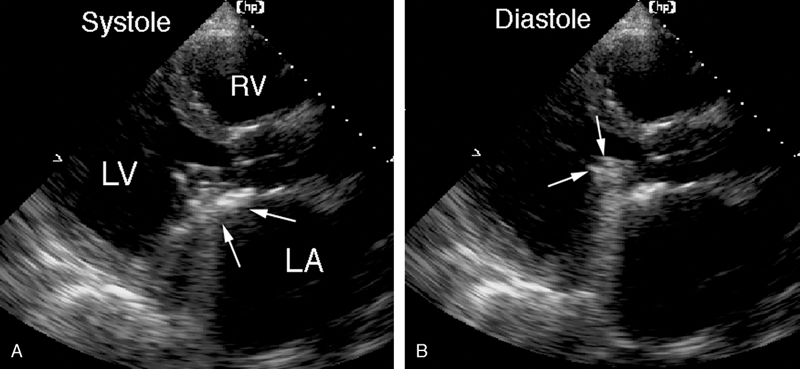

فحوصات تشخيصية لبعض امراض القلب والشرايين التاجية